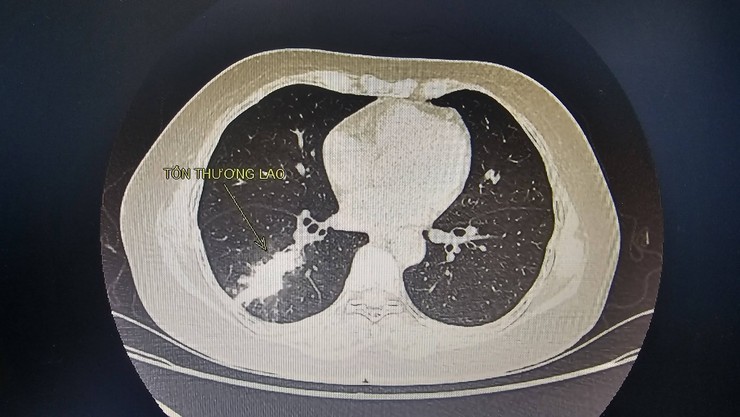

Khi ho ra máu nhiều là dấu hiệu nguy hiểm người bệnh không nên chủ quan- Ảnh 1.

Hình ảnh chụp X- quang của bệnh nhân.

Một bệnh nhân 40 tuổi, đến khám trong tình trạng ho kéo dài, đau tức ngực, sốt dai dẳng về chiều. Khai thác bệnh sử, bệnh nhân đã xuất hiện triệu chứng nhiều tuần trước, nhưng do chủ quan, cho rằng chỉ là viêm đường hô hấp thông thường nên tự mua kháng sinh uống nhiều đợt tại nhà, không đi khám chuyên khoa. Các triệu chứng không thuyên giảm mà ngày càng rõ rệt, đặc biệt là ho nhiều, đau tức ngực, sốt nhẹ về chiều và mệt mỏi kéo dài, buộc bệnh nhân phải đến bệnh viện. Các bác sĩ nhận định đây là trường hợp nghi ngờ lao phổi và nhanh chóng chỉ định làm các xét nghiệm cận lâm sàng cần thiết. Kết quả ghi nhận: dấu ấn viêm tăng cao, x-quang phổi có hình ảnh nghi ngờ viêm phổi do lao, xét nghiệm chuyên sâu xác định lao dương tính.